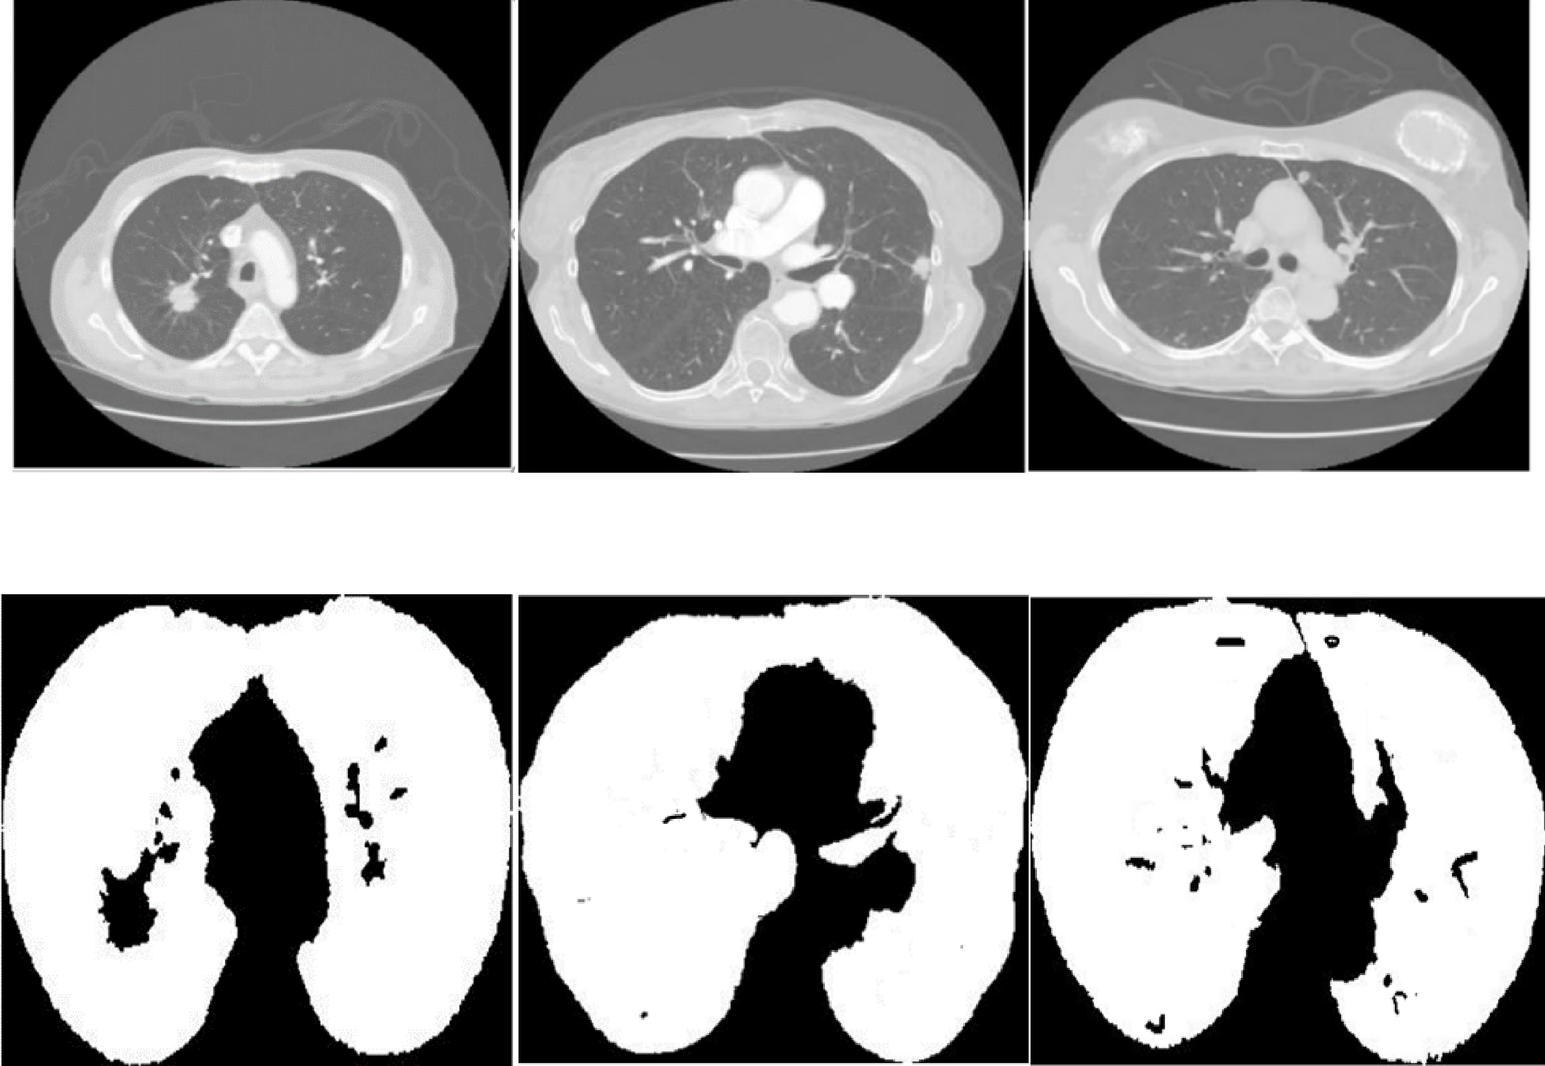

Fig. 13 | Scientific Reports